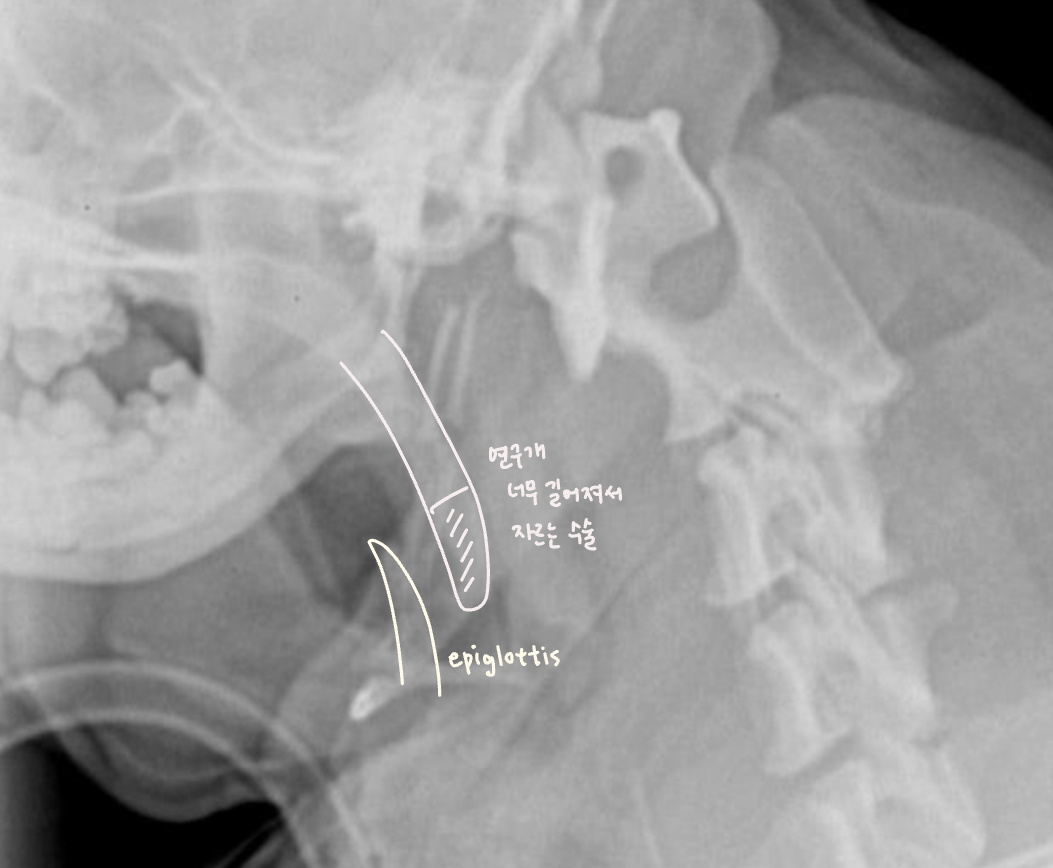

- soft palate edema & elongation (연구개노장)

- laryngeal edema, saccules, collapase, paralysis